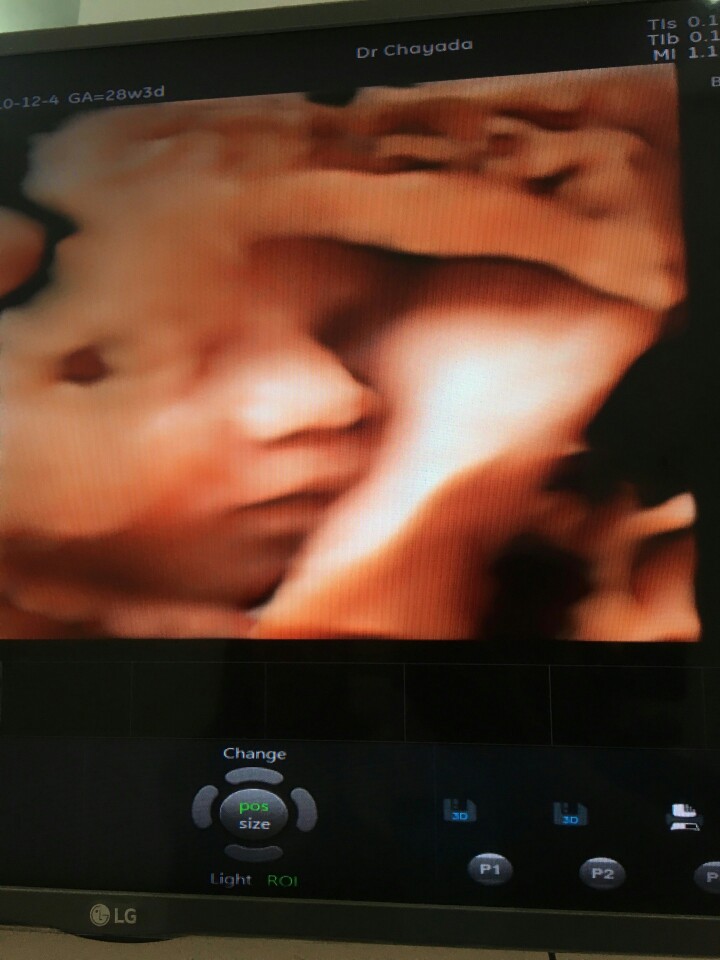

ซาวด์ที่คลีนิกค่ะ 3500 อายุครรภ์ 7 เดือน ค่ะ